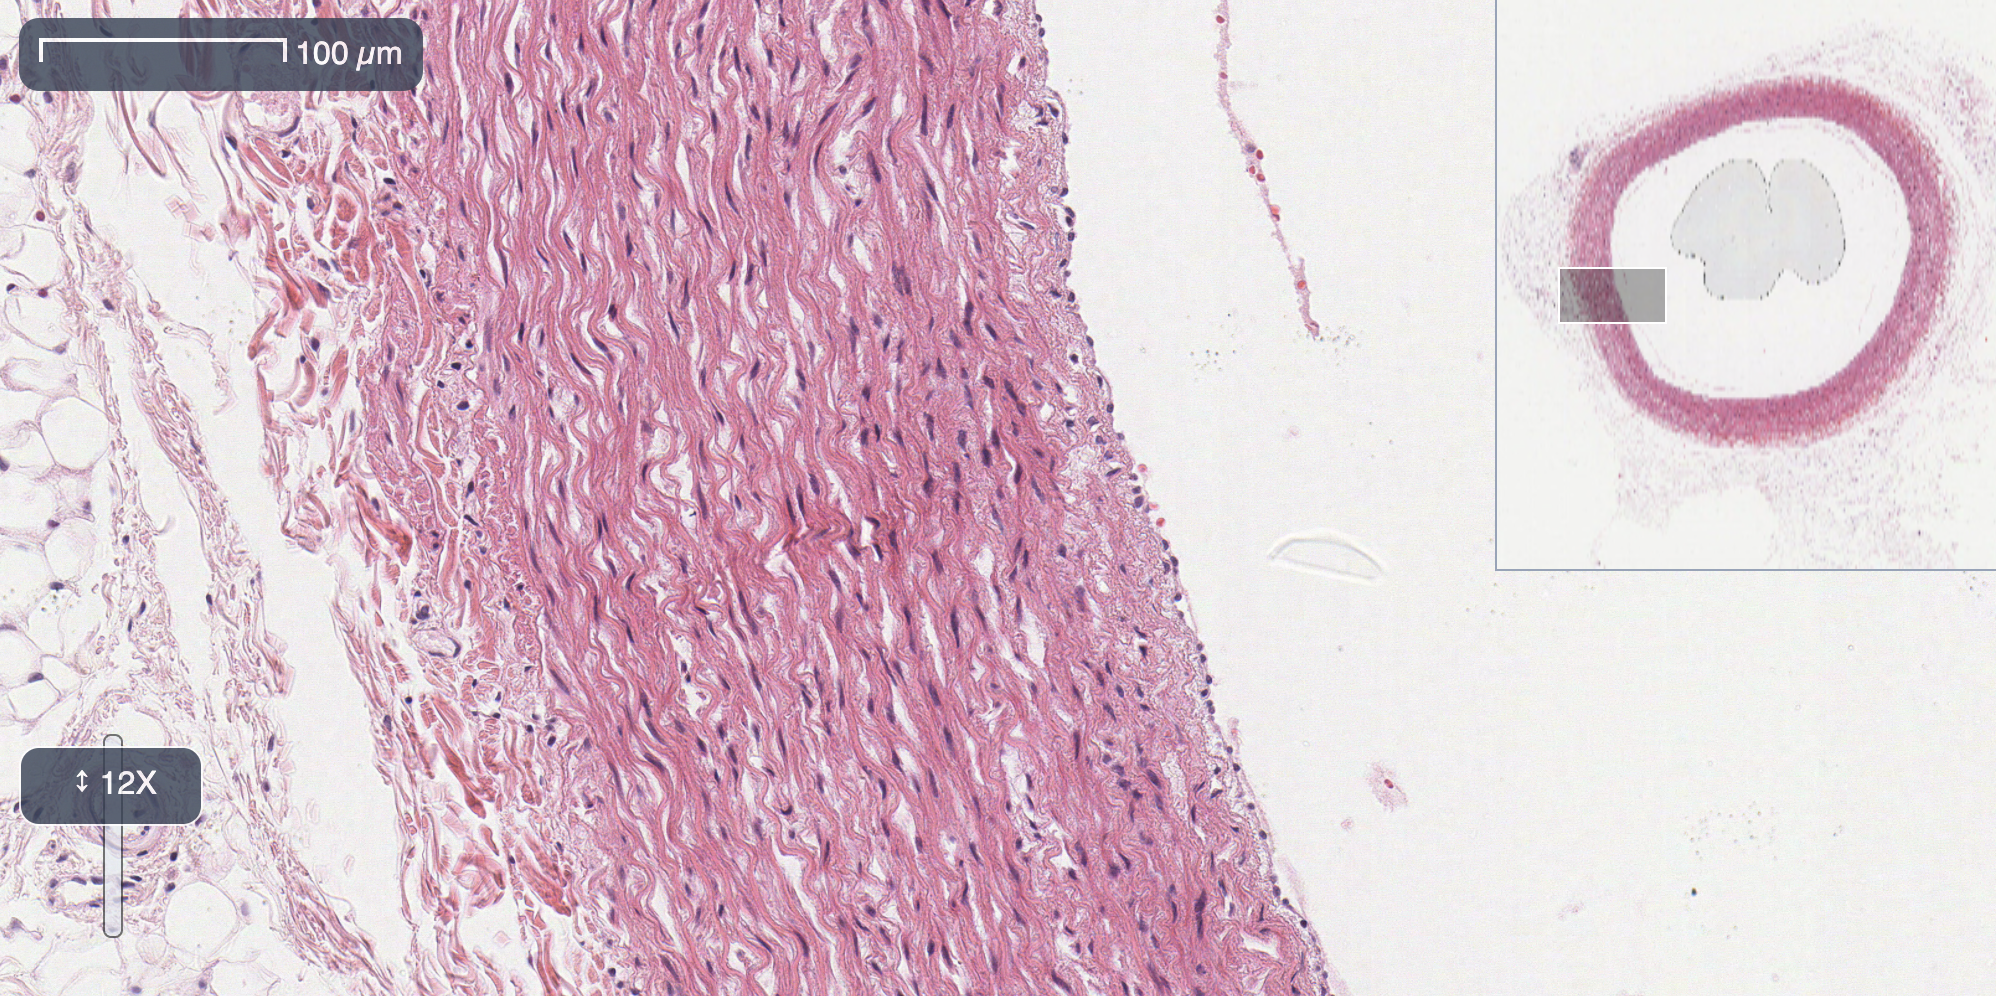

Conflux slide viewer showing an SVS file loaded and rendered in the browser

The images above are rendered directly with OpenSlideWASM in your browser. The sample viewer allows users to load and navigate an SVS from their hard disk.